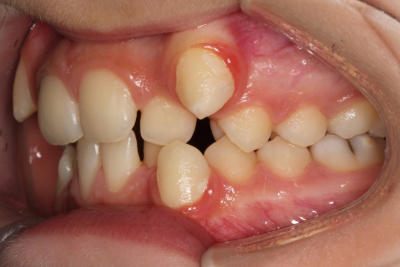

Crowding with lateral open bite – Child case